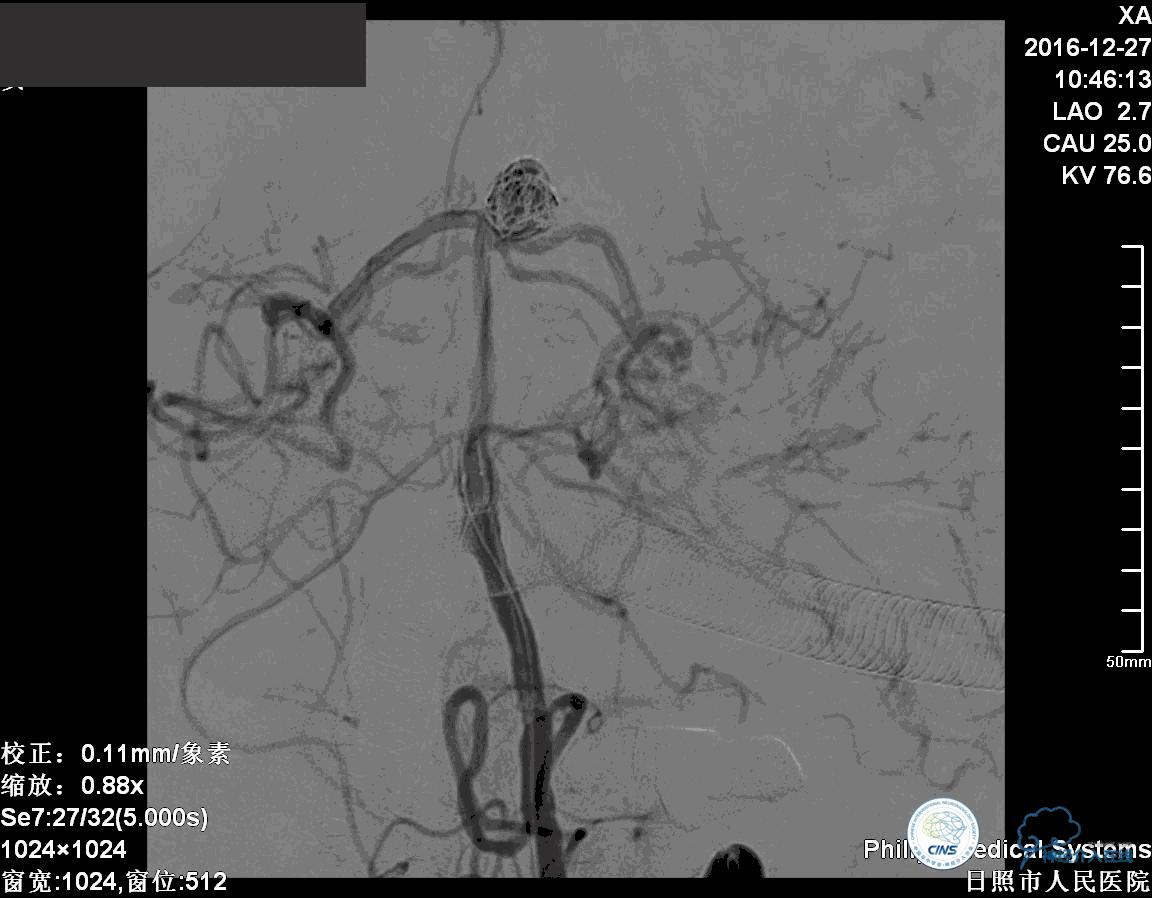

分别选择了7mmx30cm、6mmx30cm、2个4mmx15cm、3mmx8cm、2mmx8mm Target共6个弹簧圈进行栓塞。

术后